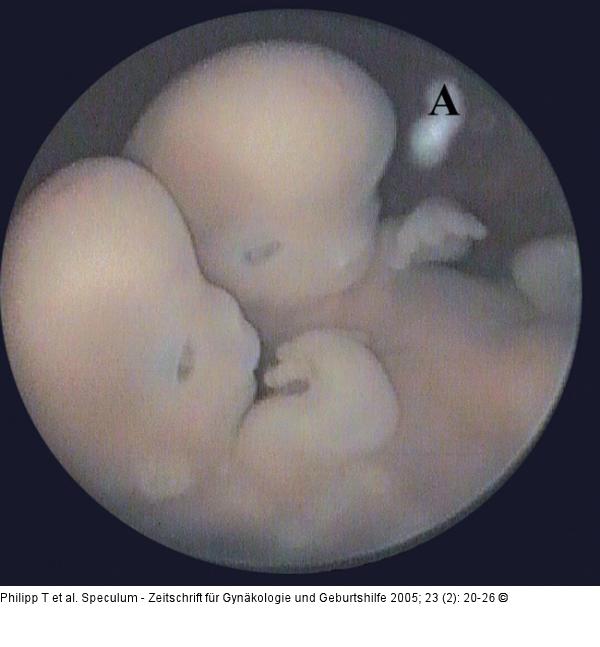

Abbildung 11: Thorakopagus Embryoskopische Aufnahme eines Thorakopagus von 34 mm SSL, von rechts seitlich. Zwei separate Köpfe und eine ausgeprägte Verschmelzung am Thorax und im oberen Bereich des Abdomens, sind zu erkennen. (A) markiert Reste des Amnions (Karyotyp: 46,XX). |

Embryoskopische Aufnahme eines Thorakopagus von 34 mm SSL, von rechts seitlich. Zwei separate Köpfe und eine ausgeprägte Verschmelzung am Thorax und im oberen Bereich des Abdomens, sind zu erkennen. (A) markiert Reste des Amnions (Karyotyp: 46,XX). |